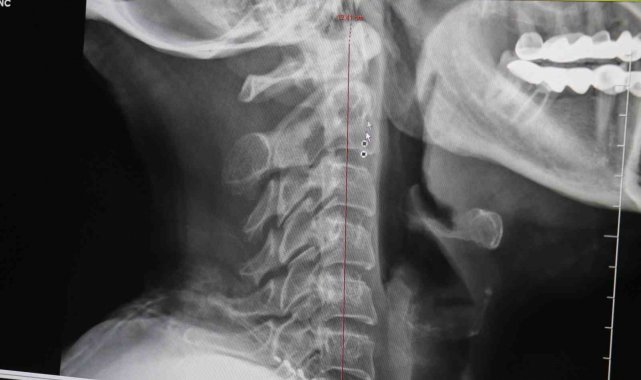

Denizli Özel Tekden Hastanesi Beyin ve Sinir Cerrahisi Uzmanı Op. Dr. Yasin Levend Özçelik, son zamanlarda artan boyun düzleşmesi hakkında önemli açıklamalarda bulundu. Op. Dr. Özçelik, boyun düzleşmesinin son zamanlarda eskiye göre daha çok sık gördüklerini belirtti. Eskiden daha çok kuaförlerde, sekreterlerde görülen bir rahatsızlık olduğunu hatta boyun düzleşmesinin ve yol açtığı boyun fıtığının sekreter hastalığı olarak geçtiğini belirtti. Bu tür hastalıkların son dönemlerde artmasının en büyük sebeplerinden birinin boynumuzu yanlış kullanmaktan olduğunu söyledi. boynun kendi doğal bir kavisi olması gerektiğini belirten Op. Dr. Özçelik, bu kavisin yumuşak bir C harfi şeklinde olduğunu ifade etti. Çeşitli yanlış davranışlar ve hareketlerin ardından kavisi koruyamadığınız zaman ise boynun önündeki veya arkasındaki kasların spazma girdiğini belirten Op. Dr. Özçelik, kasılan kasların omurların kendine doğru çektiğini ve sonrasında düzleşme denilen bir hadisenin geldiğini ifade etti.

Boynun 30 dereceden fazla eğerek yapılan her şeyin boyun kaslarında spazma yol açtığını belirten Op. Dr. Özçelik, "Bu sorunlar genellikle boynumuzu ergonomik kullanmamakla ilgili oluyor. Örneğin, boynumuz 30 dereceden fazla eğerek yaptığımız her şey boynumuz kaslarında spazma yol açabiliyor. Yani şu şekilde yaptığımız; kitap okuma, telefona bakma, pirinç seçme, dantel örme, nakış yapma vesaire gibi durumlarda boynumuzda düzleşmeye yol açabiliyor. Normalde boyunlar düz değil arkaya doğru kıvrılması gerekiyor. Hafif 'C' şeklinde bir kavisi olması gerekiyor" dedi.